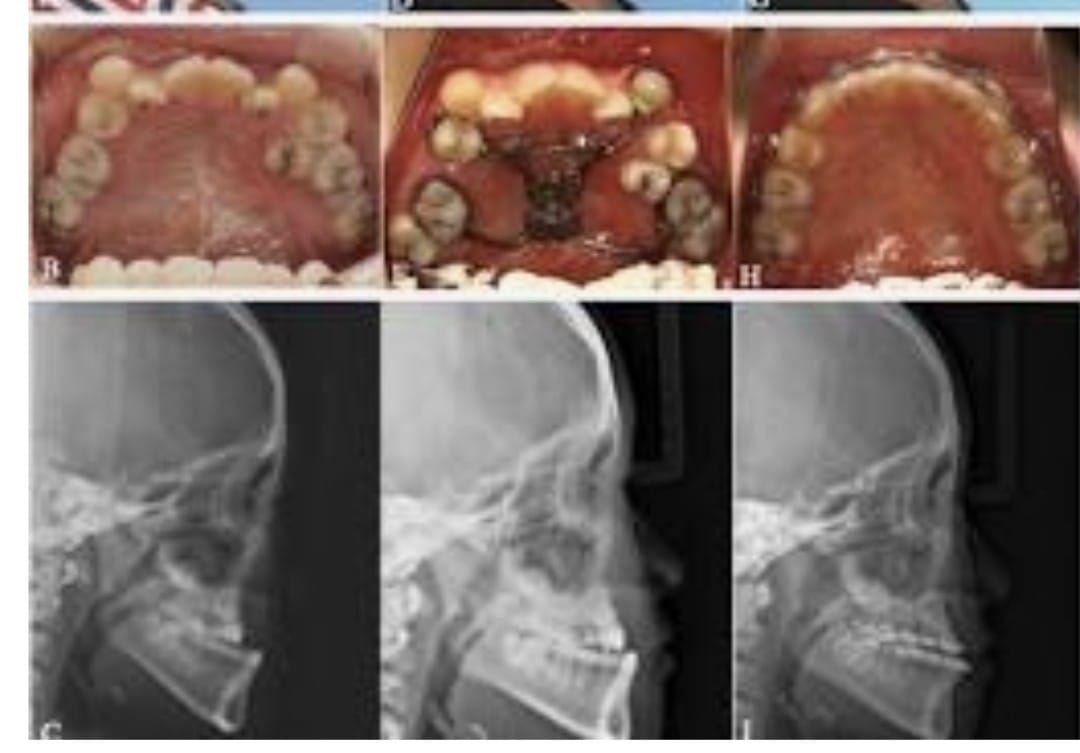

Maxillary hypoplasia is a condition characterized by the underdevelopment of the upper jaw (maxilla), which can affect both facial appearance and oral function. It often results in a sunken midface, improper bite alignment, and may contribute to breathing or speech difficulties. This condition can be congenital or develop during growth, impacting overall facial harmony and balance.

Treatment for maxillary hypoplasia focuses on correcting the position and structure of the upper jaw to improve both function and aesthetics. Depending on the severity, procedures such as orthognathic (jaw) surgery are performed to reposition the maxilla, enhance facial profile, and achieve proper bite alignment. With advanced surgical planning and modern techniques, patients can achieve improved facial balance, better oral function, and long-lasting results.

Pre-Surgical Preparation

The notes outline several steps required before undergoing these surgeries:

- Pre-surgical Orthodontics: Often needed before the actual surgery takes place. Imaging: X-rays and CT scans are required.

- Planning: Virtual surgical planning is performed on a computer, along with model surgery.